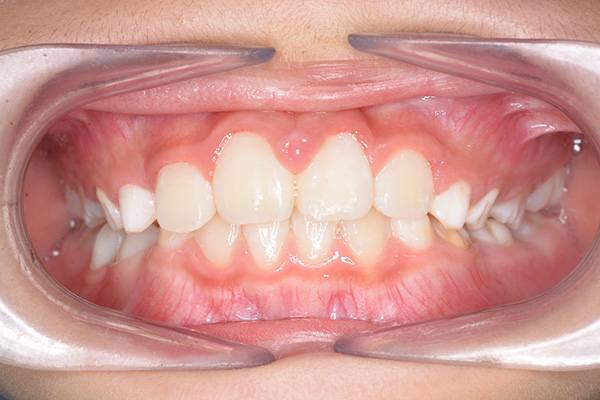

| 主訴 | 上顎前歯のでこぼこ | 診断名 | アングルⅡ級叢生症例 | ||||

|---|---|---|---|---|---|---|---|

| 初診時年齢 | 6歳9ヵ月 | 性別 | 男 | 動的治療期間 | 6ヵ月 | ||

| 既往歴として上顎正中過剰歯(2本)は抜去済み。その影響で上顎右側中切歯は捻転して萌出しており、下顎右側中切歯と早期接触が認められたため2x4(上顎のみブラケット装着)にて前歯部の改善を行った。現在は永久歯列完成まで経過観察を行い、希望があれば口元の突出感を改善するために本格矯正治療を行うことにしている。 | |

| 批評・予后 | 早期治療によって前歯部の咬合干渉は回避され、その後の永久歯への交換は順調である。 |